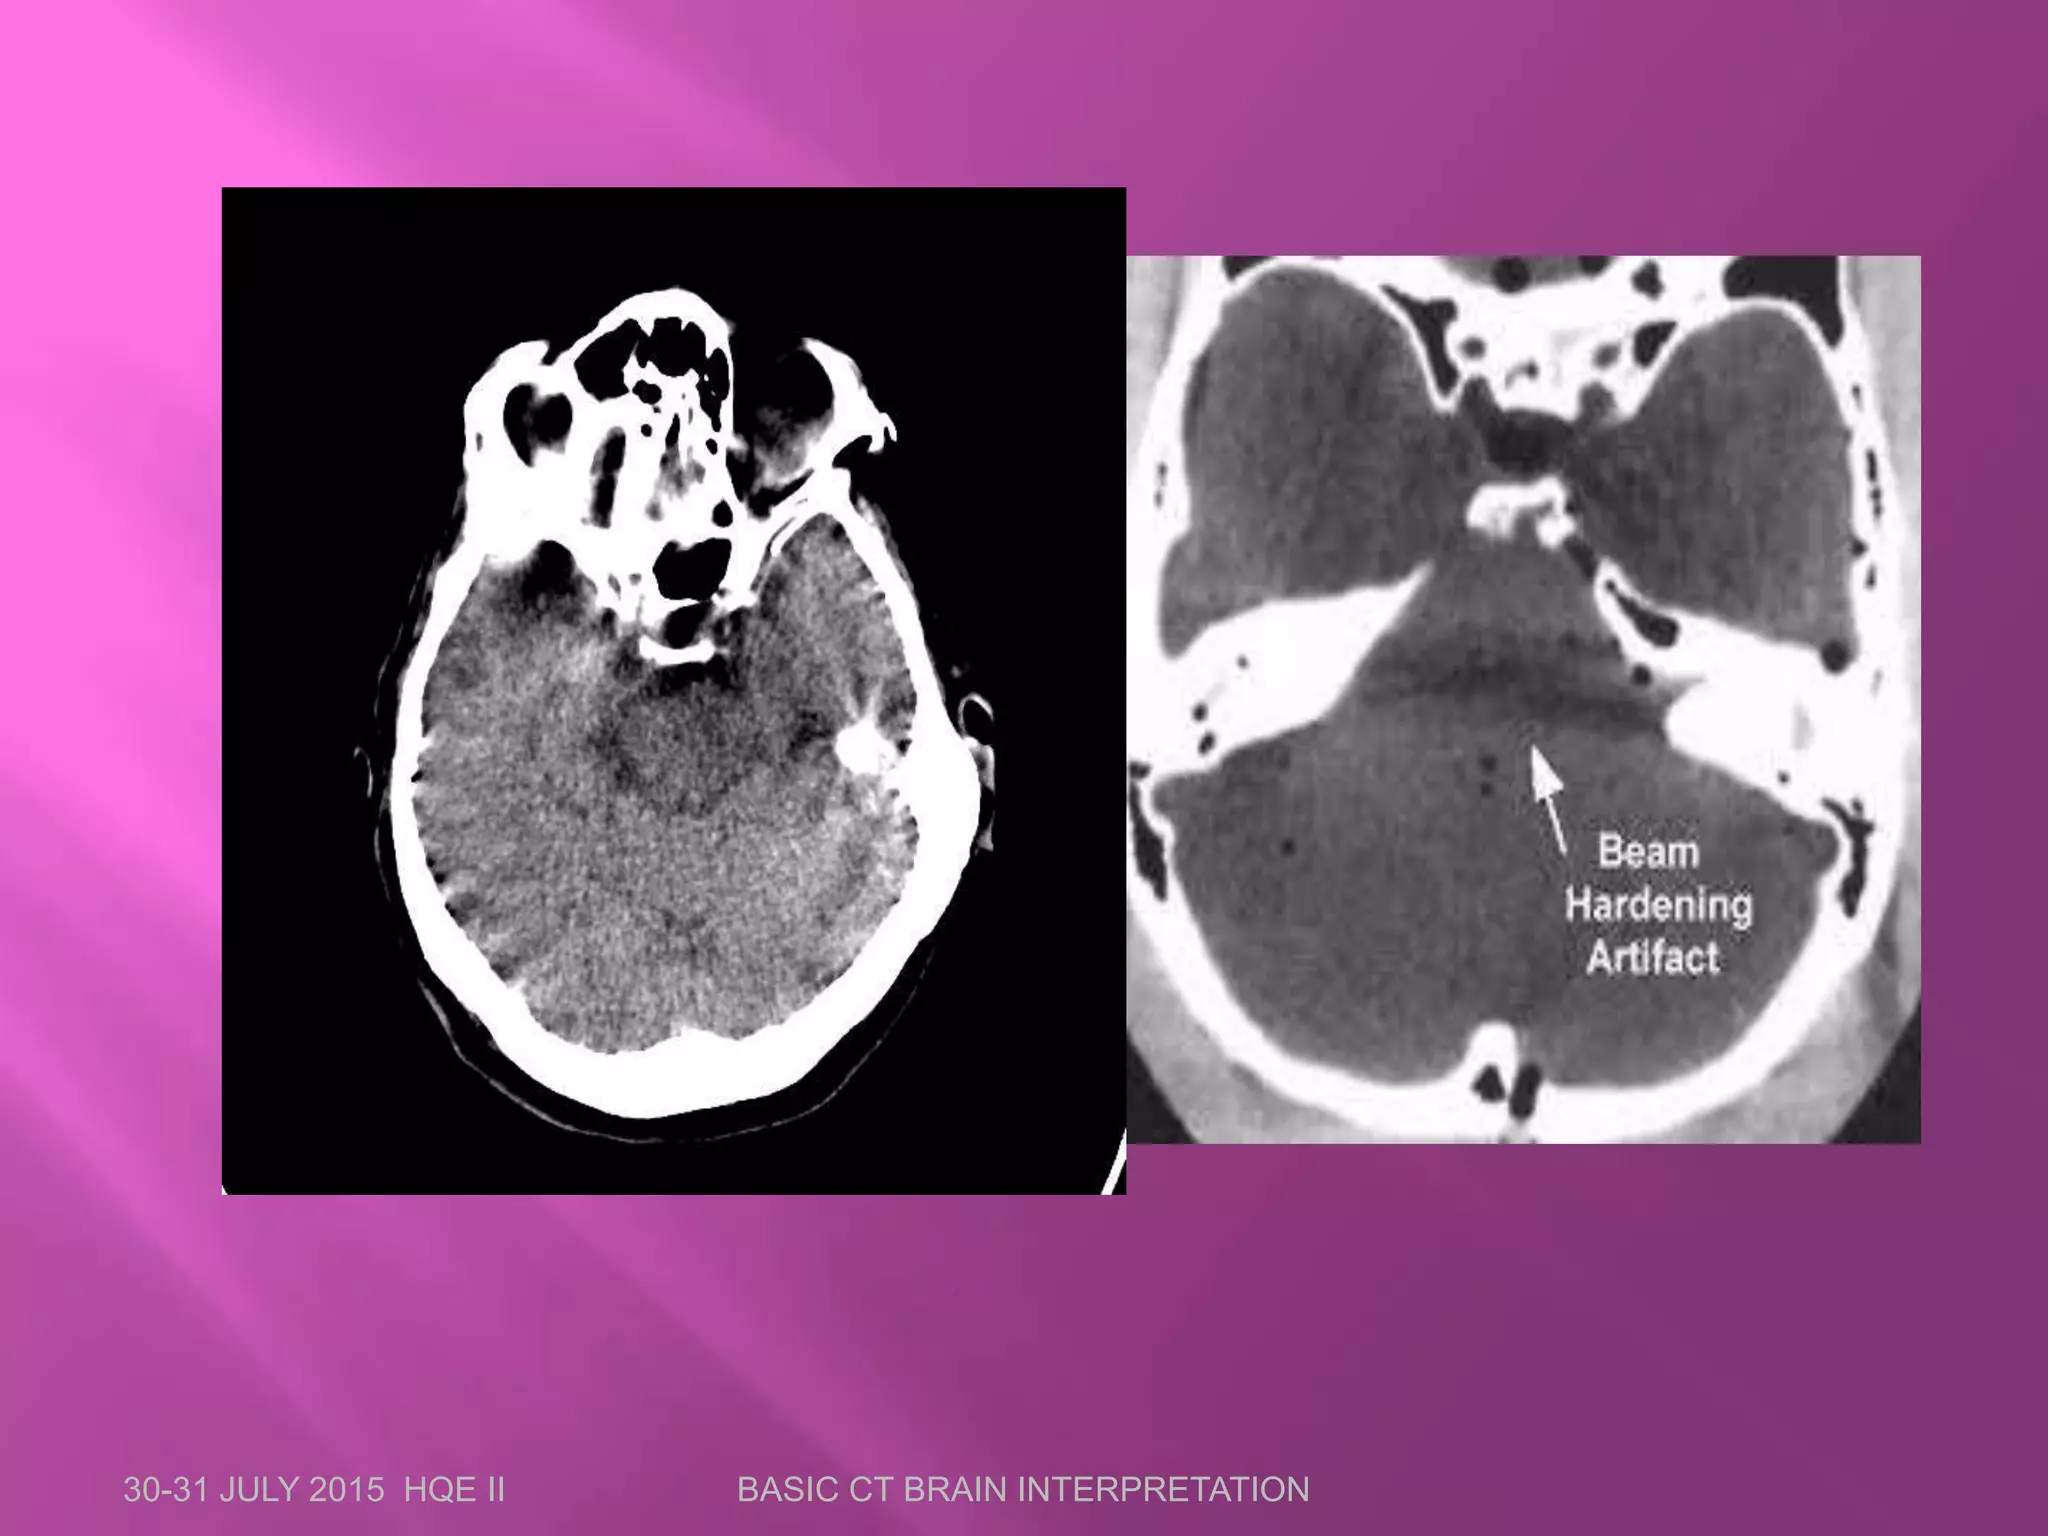

 Artifacts are distortions or errors in the image

that are unrelated to the object scanned.

 Most common artifacts in CT are:

 Motion artifacts

 Streak artifacts

 Beam hardening artifacts

 Partial voluming artifacts

 Ring artifacts